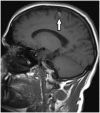

Hummingbird Sign

This indication, known as the hummingbird sign or king penguin sign, is seen on mid-sagittal T2WI, where selective atrophy of the tegmentum coupled with a relatively preserved pons gives the appearance of the head and body of a hummingbird (Fig. 17). It is characteristic of progressive supranuclear palsy (previously known as Steele-Richardson-Olszewski syndrome) (30,31).

caption a8Hummingbird sign.